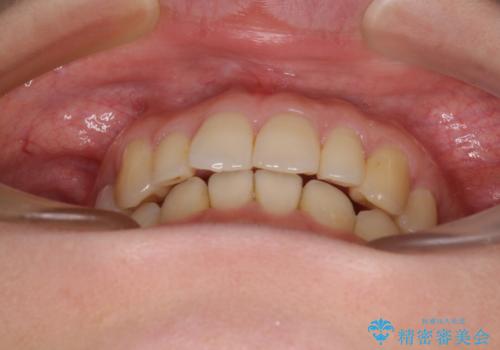

- 上顎前歯の突出感を気にして来院された患者様です。

下顎前歯2本が先天欠損しており、上顎歯列に対して、下顎歯列がアンバランスに小さい状況でした。

左右上顎側切歯2本が矮小歯であるため、上顎の抜歯ではなく、IPR(歯と歯の間を削る)と歯列全体の後方移動によってバランスを整えることとしました。

歯列のバランスが悪く、インビザライン矯正特有の奥歯の噛みにくさがなかなか改善されず、治療期間が長期化してしまいました。